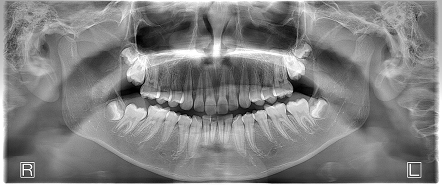

過蓋咬合 【10代・男性】

お口の中全体の写真

- 上の左右と下の左右に親知らずがレントゲン上で埋伏していましたが、年齢が若いため抜歯を行わずに矯正を行なったケースです。

- 学校の歯科検診で【歯並び悪い】とチェックがあったため矯正相談された方です。診察したところ下の前歯部に叢生を認め、前歯部に過蓋咬合(ディープバイト)で咬合関係の不正も認めました。

- 上下の叢生は改善され、過蓋咬合だった咬合関係も治って綺麗な歯並びとなりました。